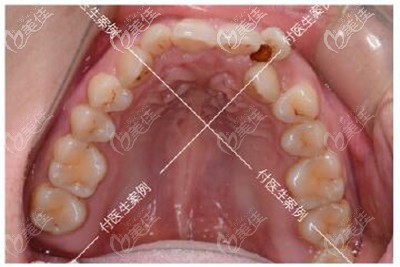

術(shù)前照片:

牙齒診斷:牙齒擁擠不齊+深覆合+單顆反頜+下頜方形牙弓

大家可能看我的牙齒圖片覺得我的問題不大,但其實我之所以下定決定要去做矯正的原因是因為我的咀嚼功能已經(jīng)完全受影響了,而且上下牙咬合導(dǎo)致我睡覺經(jīng)常磨牙、連帶著下巴后縮也常常讓我覺得自己像“凸嘴”...

深覆合牙齒矯正前后牙齒效果對比